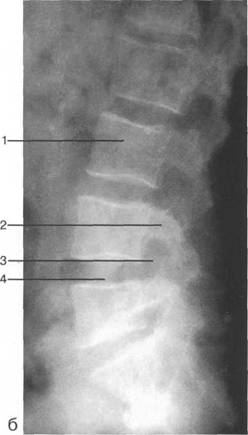

К моменту рождения (рис. 3.1) тело позвонка почти полностью состоит из к 141s183b 86;стной ткани, за исключением лимбусов, которые остаются хрящевыми. Дуга представлена двумя половинами, не слившимися ни с телом позвонка, ни между собой. Суставные отростки сохраняют перифе